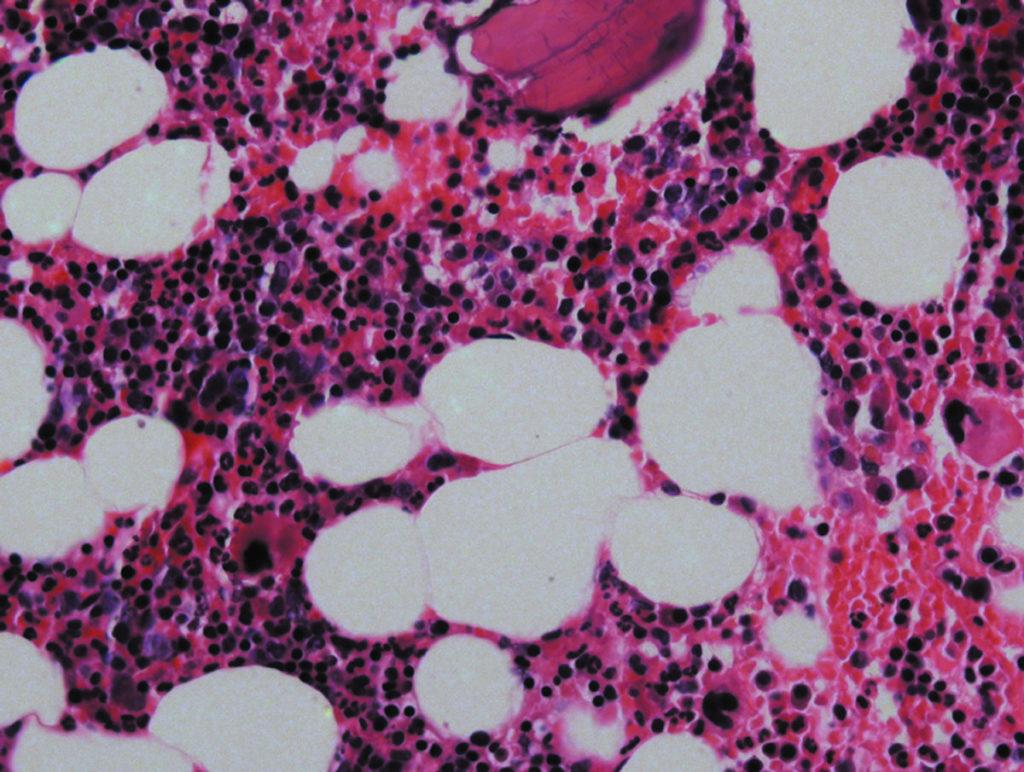

Кровь человека выглядит жидкостью, равномерно окрашенной в красный цвет, но при помещении капли крови под микроскоп открывается совсем другая картина. Вместо однородной алой жидкости в поле микроскопа видна прозрачная жидкость с плавающими в ней частицами. Большинство из них имеет красную окраску – это эритроциты, но попадаются и клетки белого цвета, которые получили название лейкоцитов.

Если эритроциты все примерно одинаковы и отличаются друг от друга только степенью зрелости, то лейкоциты более разнообразны. Они различаются по своему виду, функциям и продолжительности жизни. Разновидности лейкоцитов:

Почему лейкоцитарные клетки называются по-разному? Причиной этому стала их неодинаковая восприимчивость к красителям, которыми их окрашивают лаборанты перед исследованием в микроскопе. Эозинофилы впитывают кислый краситель эозин, базофилы лучше окрашиваются с помощью основного красящего вещества, а нейтрофилы одинаково восприимчивы к обоим типам окрашивания (рекомендуем прочитать: ).